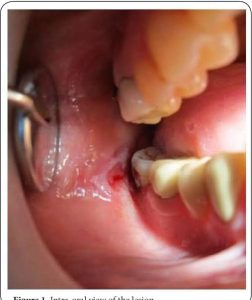

Amalgam Ve Kandidiyazis Candida

Fotoğrafların ortak yönü : amalgam-kandidiyazis

Cıva/ Merkür’ün vücutta Candida ile simbiyotik bir ilişkisi vardır ve Candida’nın çoğalmasını teşvik eder.

Cıva, nötrofillerin ve miyeloperoksidazın litik aktivitesini etkileyerek vücudun Candida albicans’ı öldürme kabiliyetini bozar.